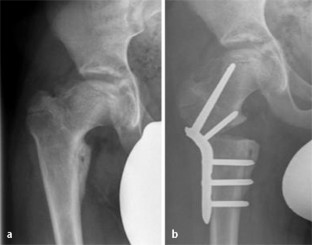

Abb. 3